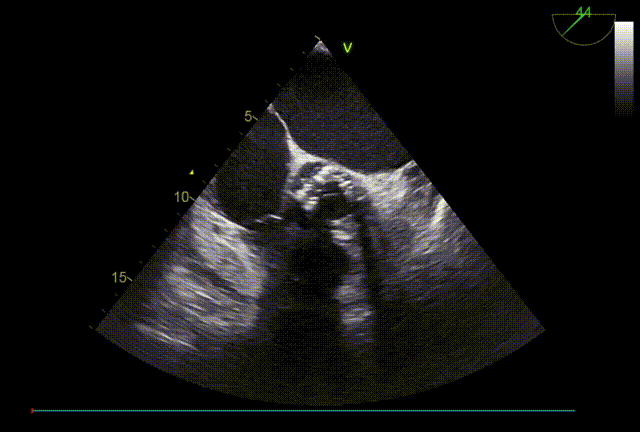

TTE入院

TTE